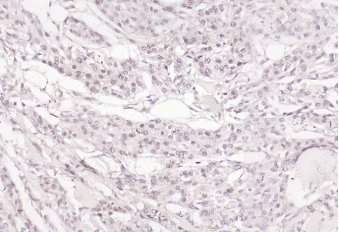

Paraformaldehyde-fixed, paraffin embedded (human glioma); Antigen retrieval by boiling in sodium citrate buffer (pH6.0) for 15min; Block endogenous peroxidase by 3% hydrogen peroxide for 20 minutes; Blocking buffer (normal goat serum) at 37°C for 30min; Incubation with (OIT3) Polyclonal Antibody, Unconjugatedat 1:200 overnight at 4°C, followed by operating according to SP Kit(Rabbit)instructionsand DAB staining.

Paraformaldehyde-fixed, paraffin embedded (human skin cancer); Antigen retrieval by boiling in sodium citrate buffer (pH6.0) for 15min; Block endogenous peroxidase by 3% hydrogen peroxide for 20 minutes; Blocking buffer (normal goat serum) at 37°C for 30min; Incubation with (OIT3) Polyclonal Antibody, Unconjugatedat 1:200 overnight at 4°C, followed by operating according to SP Kit(Rabbit)instructionsand DAB staining.